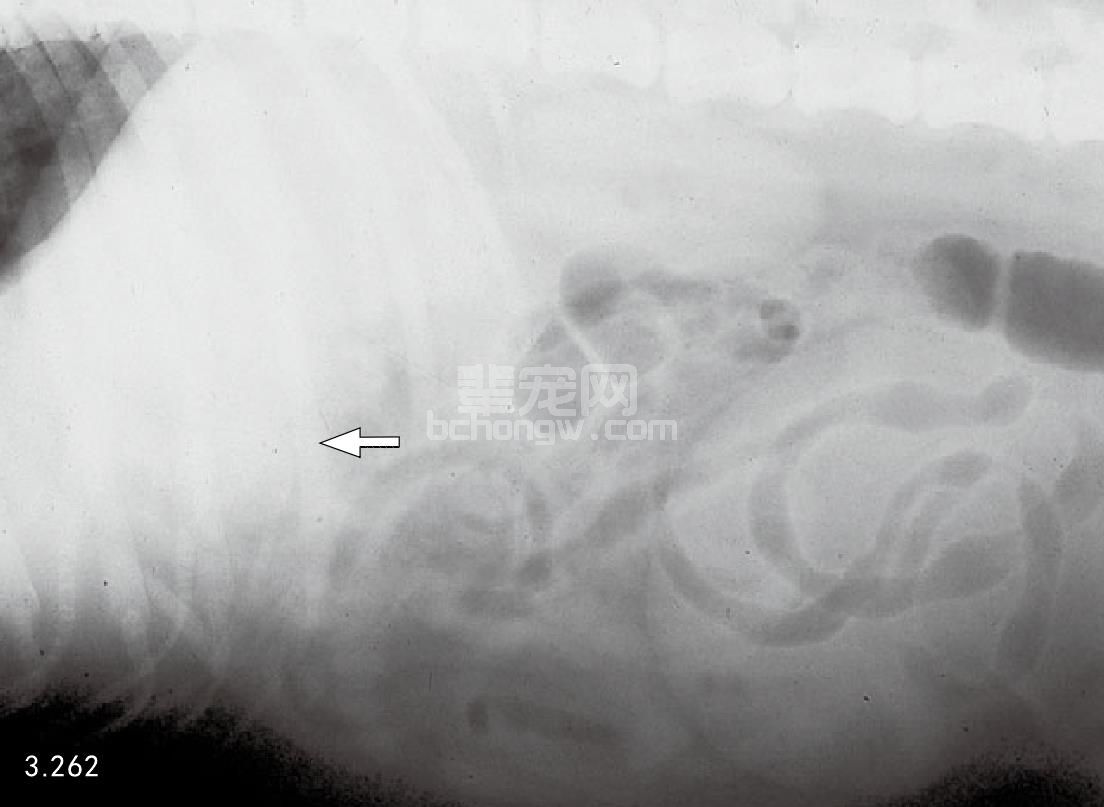

两种最常用方法是X线和超声波。犬和猫急性胰腺炎的腹部X线能显示几处异常。在轻度水肿时,可见包括胃和十二指肠从正常到轻度肠梗阻范围。更严重时,由于腹膜炎会导致以下变化:在腹腔前部由于液体密度增加,使内脏详细影像消失,右侧十二指肠移位和胃扩张。除这些典型症状外,急性胰腺炎X线显示胸腔渗漏液和肺部积液(图3.262和图3.263)。

图3.262和图3.263 犬患有急性胰腺炎的几种异常的侧面和腹背面的X线片,侧面投影(图3.262)显示腹中前部不清楚,腹前部液体密度增加,从末端到肝脏(箭头所指)。腹背面X片(图3.263)可见与十二指肠梗阻一起,单侧右上腹部液体密度增加。